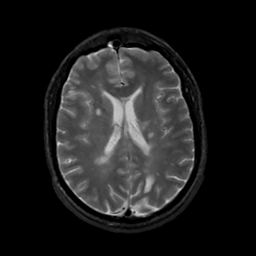

MR Study #10, April 28, 1991 -- Slice #30